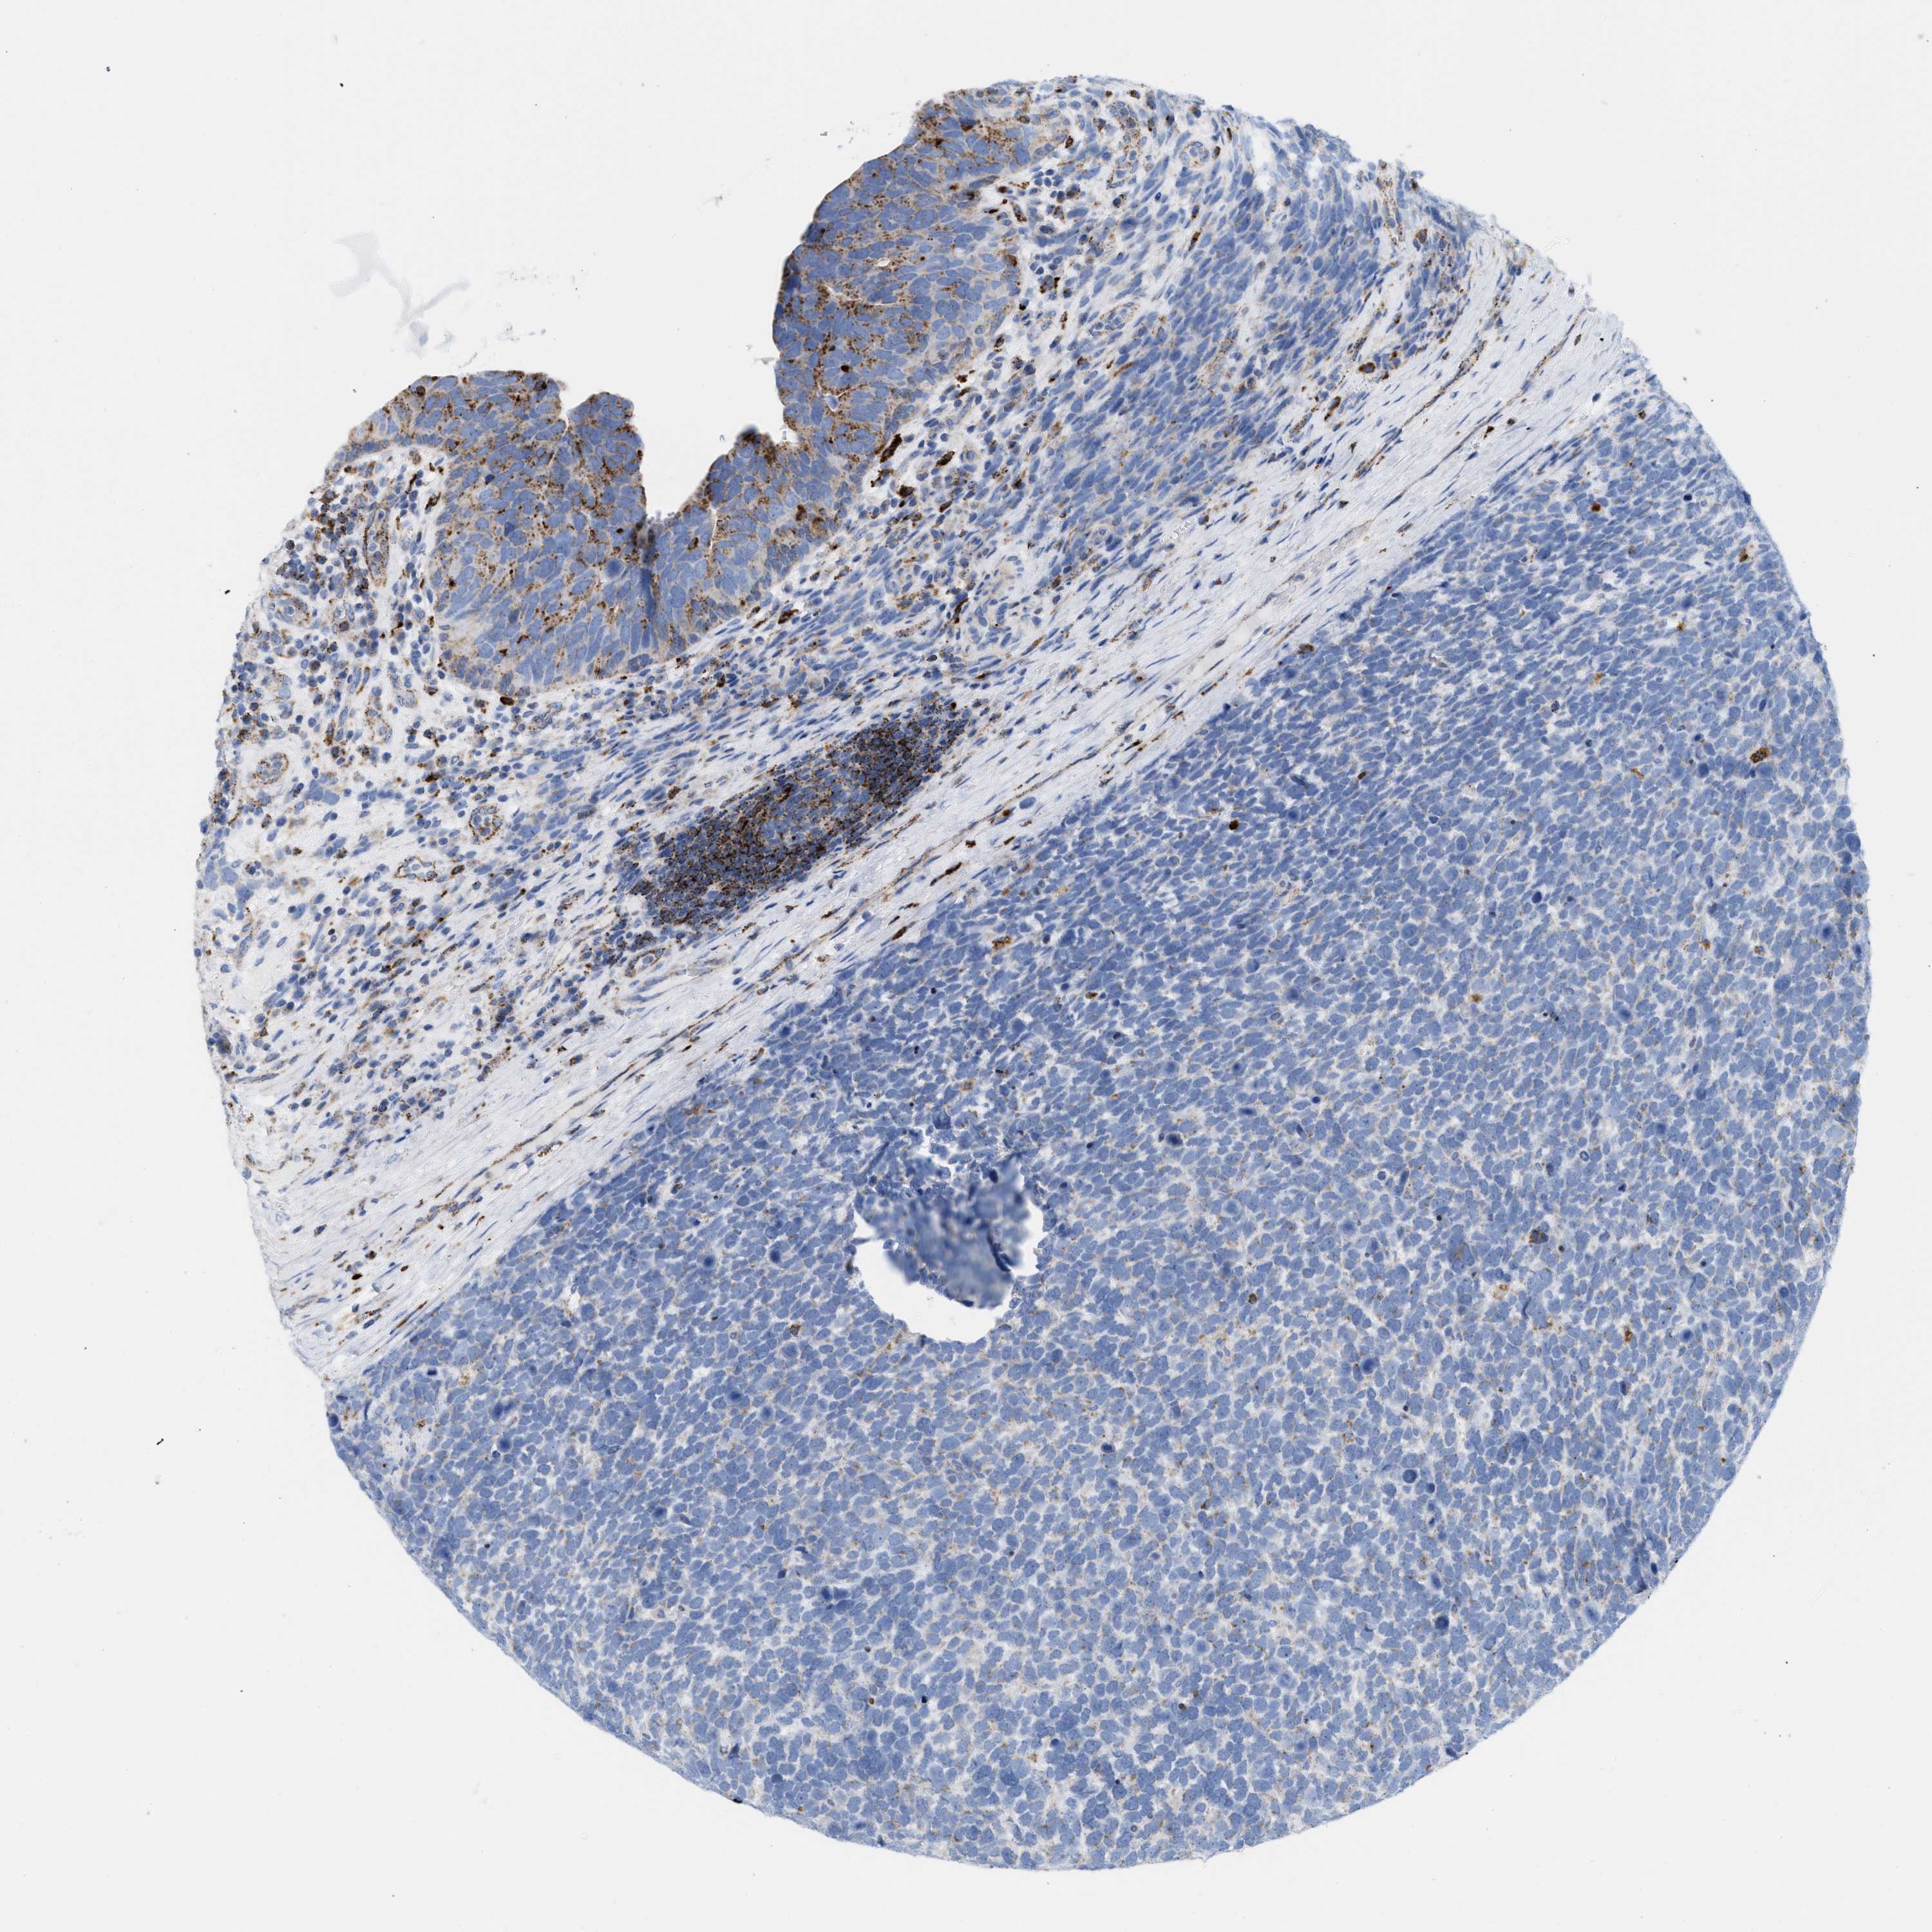

UROTHELIAL CANCER - Protein expressioni

A mouse-over function shows sample information and annotation data. Click on an image to view it in a full screen mode. Samples can be filtered based on level of antibody staining by selecting one or several of the following categories: high, medium, low and not detected. The assay and annotation is described here.

Note that samples used for immunohistochemistry by the Human Protein Atlas do not correspond to samples in the TCGA dataset.

Antibody stainingi

Antibody staining in the annotated cell types in the current human tissue is reported as not detected, low, medium, or high, based on conventional immunohistochemistry profiling in selected tissues. This score is based on the combination of the staining intensity and fraction of stained cells.

Each image is clickable and will lead to virtual microscopy that enables deeper exploration of all samples and also displays staining intensity scores, fraction scores and subcellular localization as well as patient and tissue information for each sample.

Antibody HPA018036

Antibody HPA061701

Urothelial carcinoma, Low grade

Urothelial carcinoma, High grade

Urothelial carcinoma, NOS